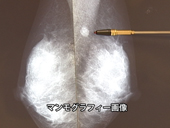

【乳がんは増加しています】

女性特有のがんの中で子宮ガンは減少傾向にあるにも係らず、乳がんは逆に増加しています。

40代に多く見られる乳がんは、早期発見・早期治療を行えば克服できる病気です。